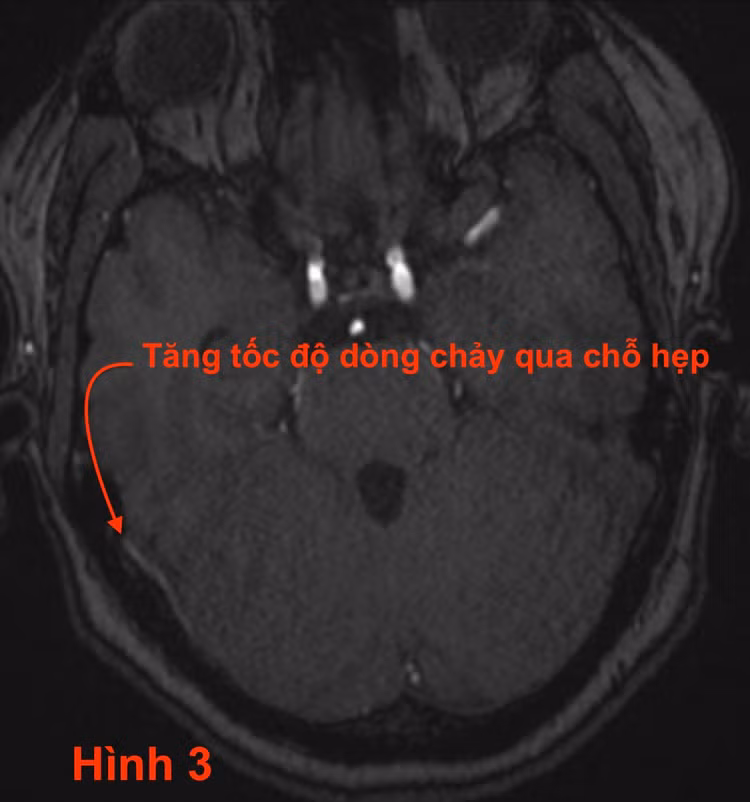

- Chẩn đoán xác định dựa vào CTA và MRI (chứ không phải DSA): Phim chụp CT có tiêm thuốc thấy hẹp xoang tĩnh mạch ngang bên phải (hình 2). Vị trí hẹp mạch này có tốc độ dòng chảy cao hiện hình trên xung TOF3D của MRI (hình 3).